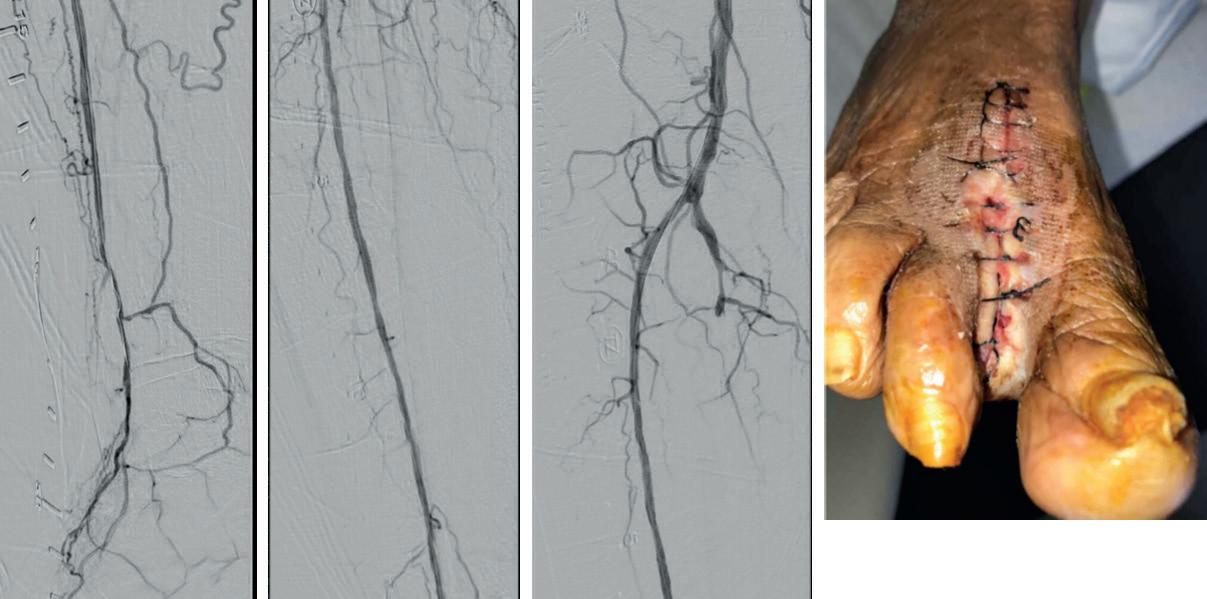

A 75-year-old female patient with diabetes and end-stage kidney disease (ESKD) presented with progressive right second toe swelling ulceration with gangrene and rest pain (Figure 1). There was extensive osteomyelitis and underlying tissue injury which required a planned amputation of the second toe. We were consulted prior to amputation for angiography, which demonstrated patent inflow vessels but severe BTK tibial disease. The baseline angiogram is shown in Figure 2. There was no inline flow to the foot, with occlusion of the anterior tibial, posterior tibial and peroneal arteries (Figure 2a). There was reconstitution of the peroneal artery, with partial filling of the posterior circulation via the posterior communicating artery. There was reconstitution of the anterior circulation with a visible small dorsalis pedis artery (Figure 2b).

Given the angiosome of the tissue loss, we elected to pursue opening the anterior tibial CTO. Access with a 5F, 70cm sheath was used from a contralateral femoral approach. Using a 0.014” microcatheter and wire escalation, we were able to cross into the true distal lumen of the distal anterior tibial circulation using a 12-gram tipped guidewire (Figure 3a). A 2.5mm Shockwave E8 was used for multiple treatments along the entire length of the CTO segment (Figures 3b, 3c). Post IVL therapy, angiography showed brisk flow through the anterior tibial and into the distal anterior circulation of the foot (Figures 4a-c). This improvement in circulation allowed for this patient to undergo her planned second toe amputation with primary close (Figure 4d).